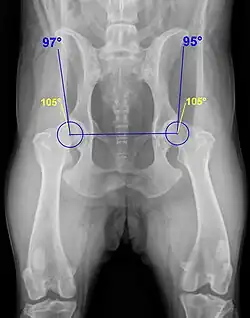

Ein wesentliches Auswertungskriterium ist der Norberg-Winkel. Er ist als der Winkel definiert, der zwischen der Verbindungslinie der Zentren der beiden Oberschenkelköpfe und dem jeweiligen vorderen Pfannenrand abgetragen wird (siehe Abbildung). Bei einem HD-freien Tier sollte er mehr als 105° betragen (gelbe Linien).[3]

Die Ausbildung der Hüftgelenke und der Norbergwinkel zeigen aber auch einige rassetypische Variationen, was bei der Auswertung durch die vom jeweiligen Zuchtverband bestallten Gutachter Berücksichtigung findet.[5]